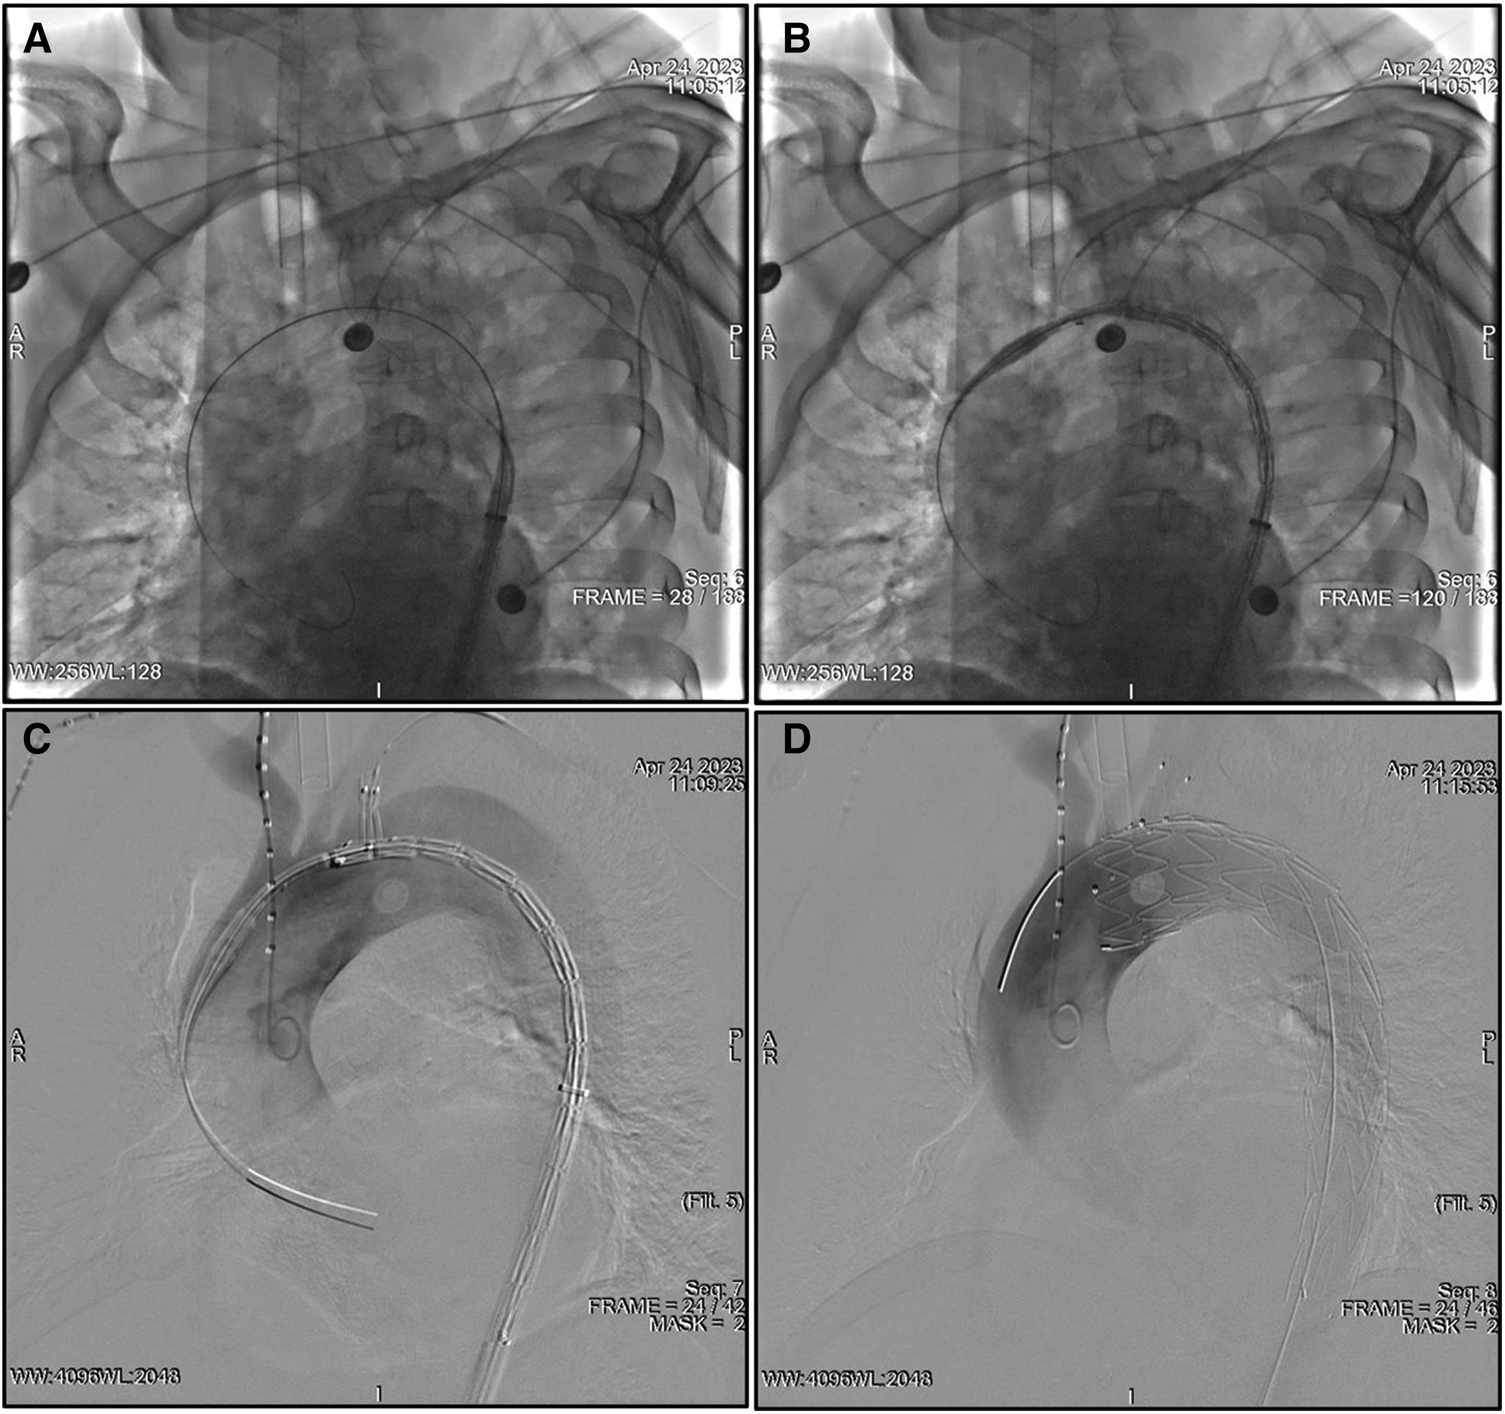

After the aortography was finished, a 5F pigtail catheter along with a guidewire was delivered from the RFA into the ascending aorta and then exchanged for a super stiff guidewire. The traction wire of the branched section was threaded into the MPA catheter from the RFA to the LBA, and the main body was introduced along the stiff guidewire from the RFA into the descending aorta (Figure 1A). The catheter and traction wire were continuously moved along the advancement of the main body. The delivery system was rotated until the branch was located at the greater curvature of the aortic arch. While the outer sheath of the main body stayed in the descending aorta, the stent graft within the soft inner sheath was delivered into the appropriate location in the arch (Figure 1B). The soft sheath was removed, and the branched section was pulled into the LSA by drawing the traction wire (Figure 1C). The main body was quickly released by withdrawing the trigger wire, and the branched section was subsequently deployed by withdrawing the traction wire and removing the “cap” (Figure 1D). Aortography was performed immediately to evaluate the branch patency and to reveal whether the intimal tear was well-sealed or an endoleak had occurred. Technical success was defined as the instant postoperative aortogram demonstrating complete exclusion of the entry tear, preserved LSA patency, and the absence of an endoleak. Each patient was given aspirin (100 mg/day) after the operation.

Figure 1

TEVAR using the Castor unibody branched stent graft for TBAD. (A) The traction wire of the branch section was drawn into the catheter from the RFA to the LBA, and the main body was advanced over the super stiff guidewire into the descending aorta. (B) The outer sheath remained in the descending aorta, and the stent graft within the soft sheath was advanced into the arch. (C) The branch section was drawn into the LSA by removing the soft sheath. (D) The main body was deployed, and, subsequently, the branch section was released by drawing the traction wire. LBA, left brachial artery; LSA, left subclavian artery; RFA, right femoral artery; TEVAR, thoracic endovascular aortic repair; TBAD, type B aortic dissection.